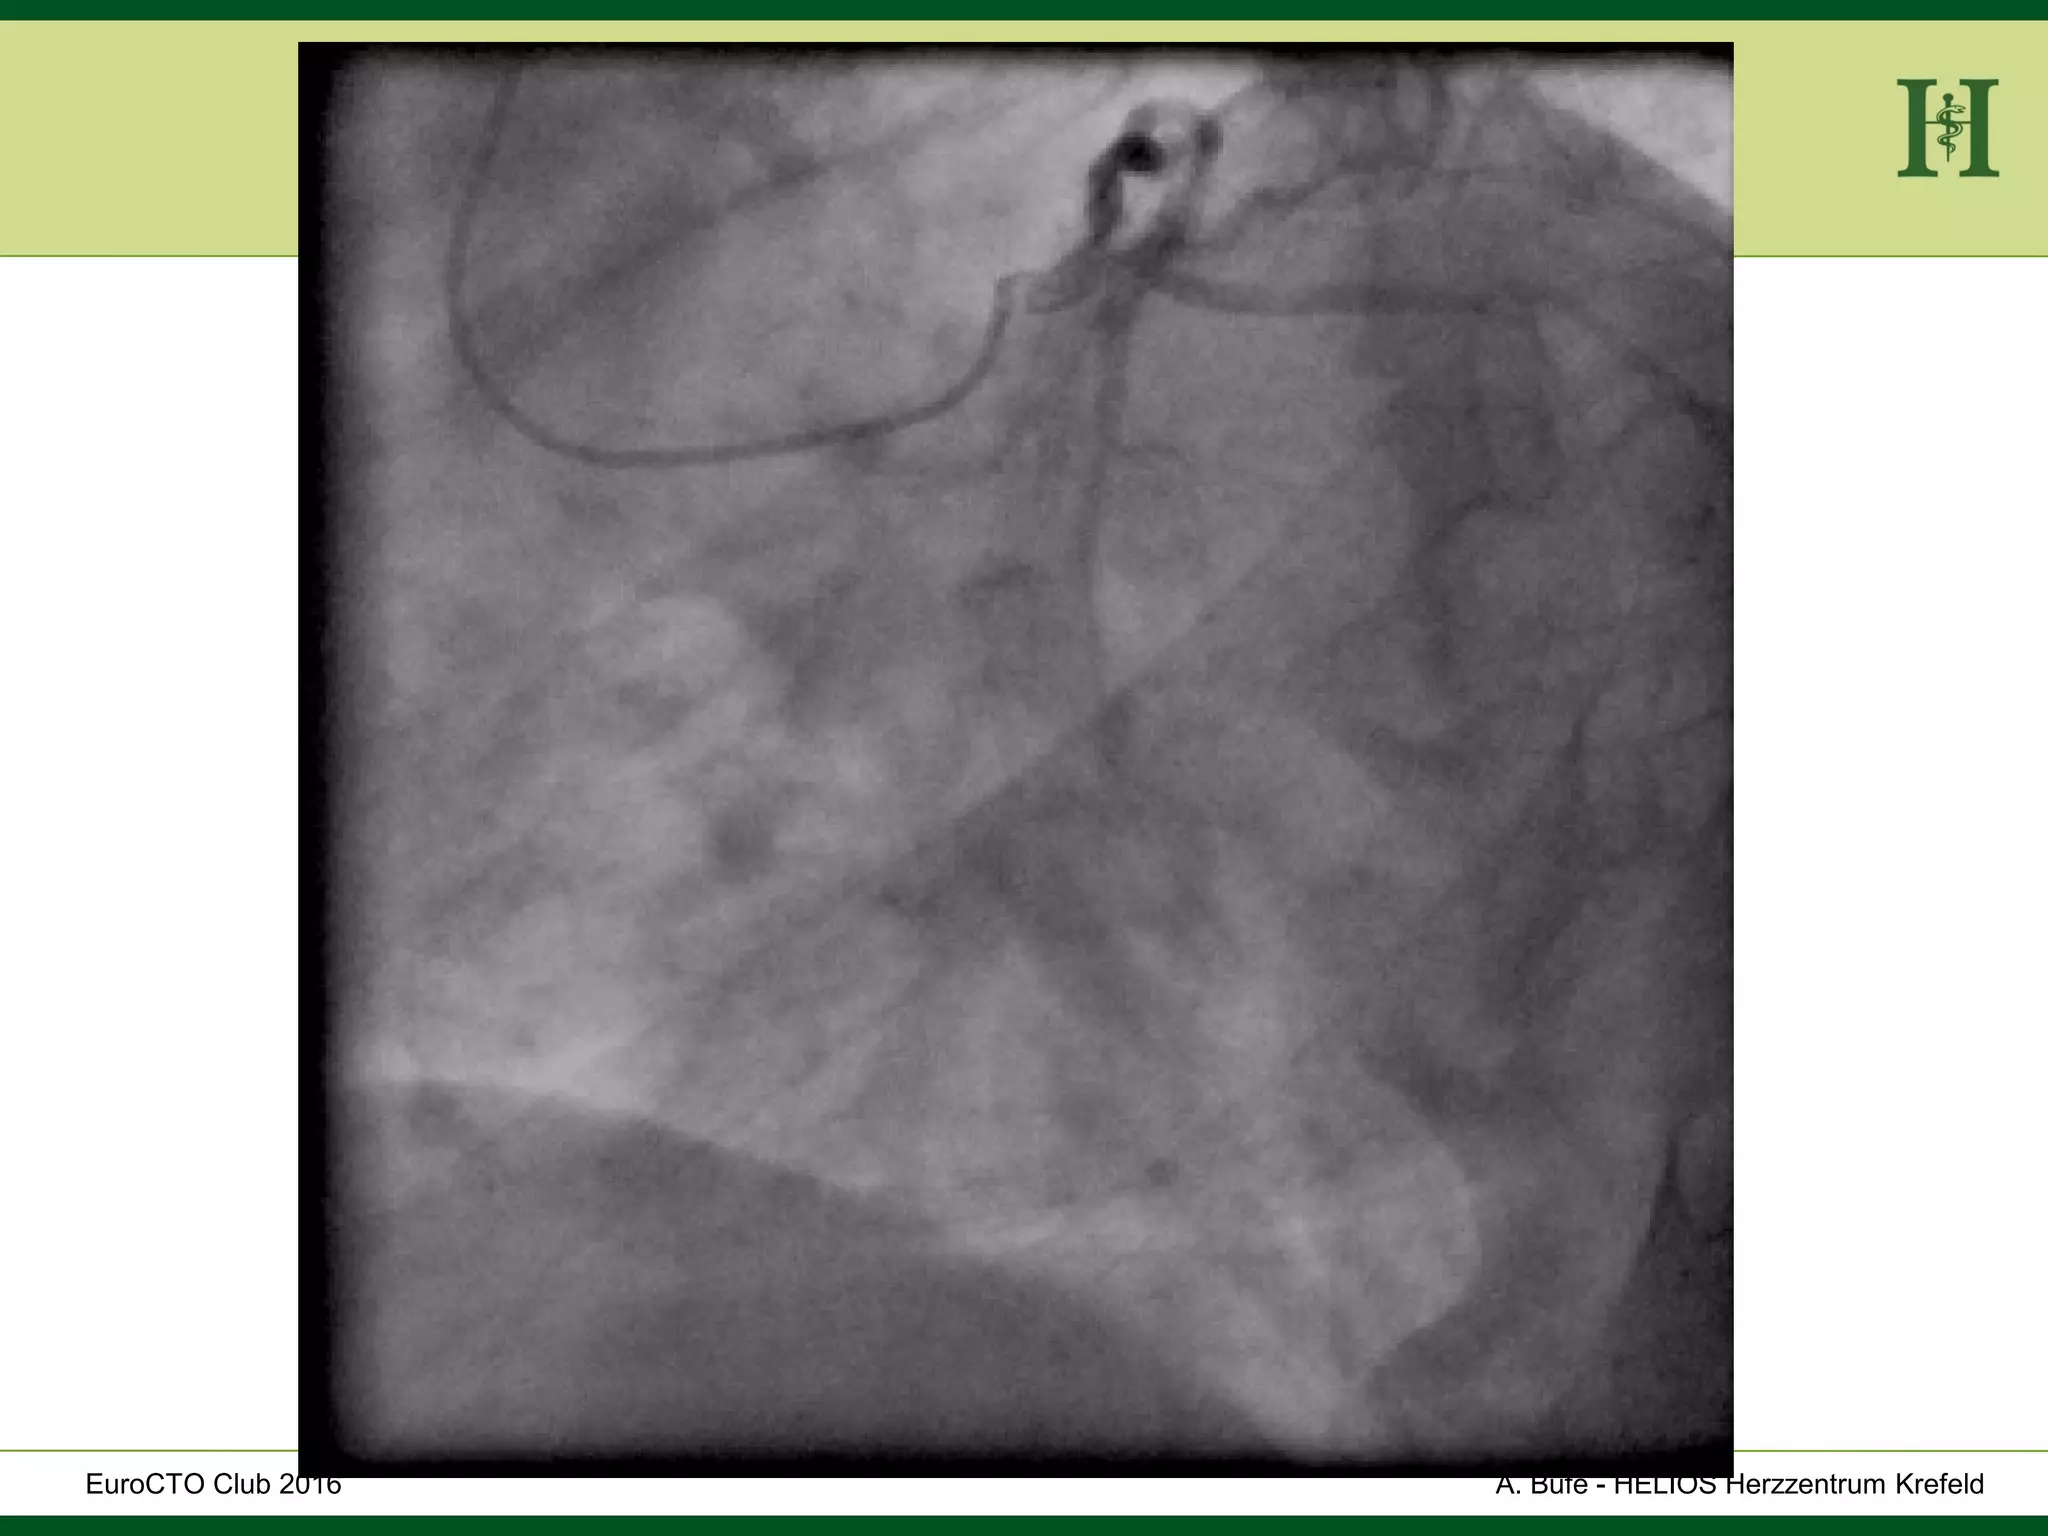

Male Patient, 55 years old

History:

 PCI 2015 with DES in LAD and in proximal RCA and

in PLD

 Angina pectoris CCS III for 7 months

 170cm, 75Kg

 RF: HLP, hypertension, smoking, HLP, familiy history

 Echo: Normal LV-Function, EF 65%

 Ischaemia inferior (MRI)